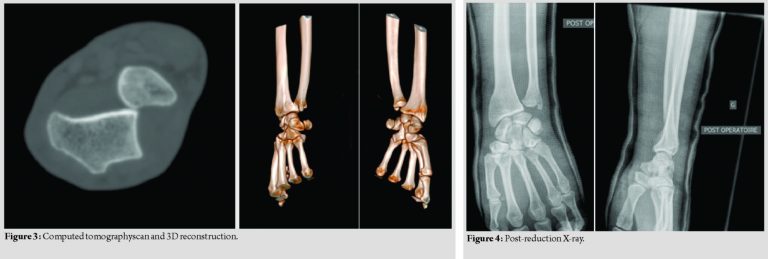

Mobility in flexion-extension was preserved. Pronation and supination were blocked and painful. The patient did not have a neurovascular deficit. Edema helped diagnosis. The ulnar head, palpable, was prominent in volar side. Diagnosis was supposed on the AP wrist and lateral views (Fig. 2) and confirmed with a computed tomography (CT)scan (Fig. 3). A radiological series including forearm and elbow X-rays confirmed the isolated character of the lesion. The patient was managed in the operating room under general anesthesia. Reduction by a closed manipulation was performed. In forced pronation, the operator maintained volar pressure on the ulnar head. The reduction was confirmed by the perception of a jerk. Post-reductionX-rays(AP, lateral, and dynamic pronosupination) made at the operating room confirmed the reduction. The test was performed in full flexion-extension and full pronation-supination. The perfectly stable aspect of the DRUJ made it possible to allow a non-operative management and avoid temporary stabilization with K-wire(Fig. 4).

The patient was immobilized in an above-elbow plaster cast for 6 weeks with the wrist in supination. At 8 days, a magnetic resonance imaging (MRI) was performed to complete the assessment of ligament injuries. No lesions of the interosseous membrane were found. A disruption of the triangular fibrocartilage complex (TFCC) at the ulna styloid and injury to the ligamentum subcruentum was found without the need for surgical intervention (Fig. 5). The patient was clinically and radiographically reassessed at the 2nd, 4th,and 6th weeks. At the control X-rays, ulna was in a satisfactory position allowing the plaster to be removed at the 6th week. An active physiotherapy was started at a rate of 3 sessions per week. The patient was seen again at the 12th week. Wrist was painless and stable both in flexion-extension (80°–50°) and pronation-supination (70°–70°). Control X-rays showed a non-arthritic wrist. The patient began to work at the 9th week. Martial arts began at the 14th week without limitation. The patient was assessed at the 6th month and 1 year. Ranges of motion at each assessment are resumed in [Table 1]. There were no sequelae and no evidence of arthrosis on the X-ray. Quick Dash at the last follow-up was equal to 0.